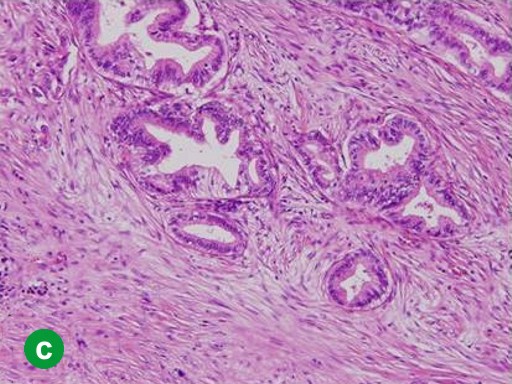

In January 2008, the patient complained of hydrodipsia and polyuria, and was diagnosed with diabetes mellitus. An abdominal CT scan revealed a 3 cm tumor in the tail of the pancreas (Figure 2a). Tumor marker (CEA and carbohydrate antigen (CA) 19-9) levels were within the reference limits, and had been throughout previous monitoring. Recurrence was confirmed using FDG-PET at 84 months after the initial operation. The FDG-PET hot spot corresponded with the tumor location shown by the CT scan (Figure 2b). The patient underwent surgery in June 2008. An intra-operative pathological examination indicated an adenocarcinoma of the remnant pancreas. A remnant distal pancreatectomy with a splenectomy was performed. The histopathological findings for the second neoplasm were similar to those of the initial lesion (Figure 2c). Carcinoma cells had invaded vessels, lymph ducts and neurons, and there were lymph node metastases (T3N1M0; R0; pathological stage: IIB). The patient was alive at 10 months after the second operation without any recurrence.

|

Figure 2. Case#1: second operation. a. A tumor approximately 3 cm in diameter was detected in the pancreatic tail on abdominal CT. b. A hot spot in FDG-PET corresponded to the tumor site on CT. c. A well- or moderately-differentiated tubular adenocarcinoma similar to the initial pancreatic cancer was detected. Mild atypical cells with a slightly swollen nucleus formed an irregular ductal structure and invaded the parenchyma. (H&E stain, x100). |